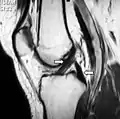

و في بعض الحالات يتم اللجوء لعمل رنين مغناطيسي للتأكد من التشخيص والتأكد من عدم وجود إصابات أخرى بالركبة مثل قطع الغضاريف الهلالية.